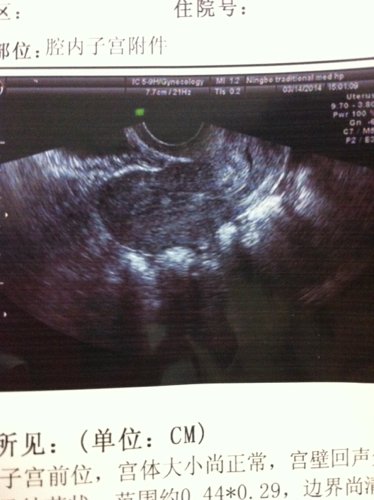

彩超,超声所见(单位CM):子宫前位,宫体大小尚正常,宫壁回声欠均,宫腔居中,双层内膜厚0.57,局部回声增强,呈结节状,范围约0.44*0.29,边界尚清。双侧卵巢大小正常,内部回声无殊,双侧附件区未见明显异常包块。盆腔内见少量游离液体,子宫直肠窝分离1.25。